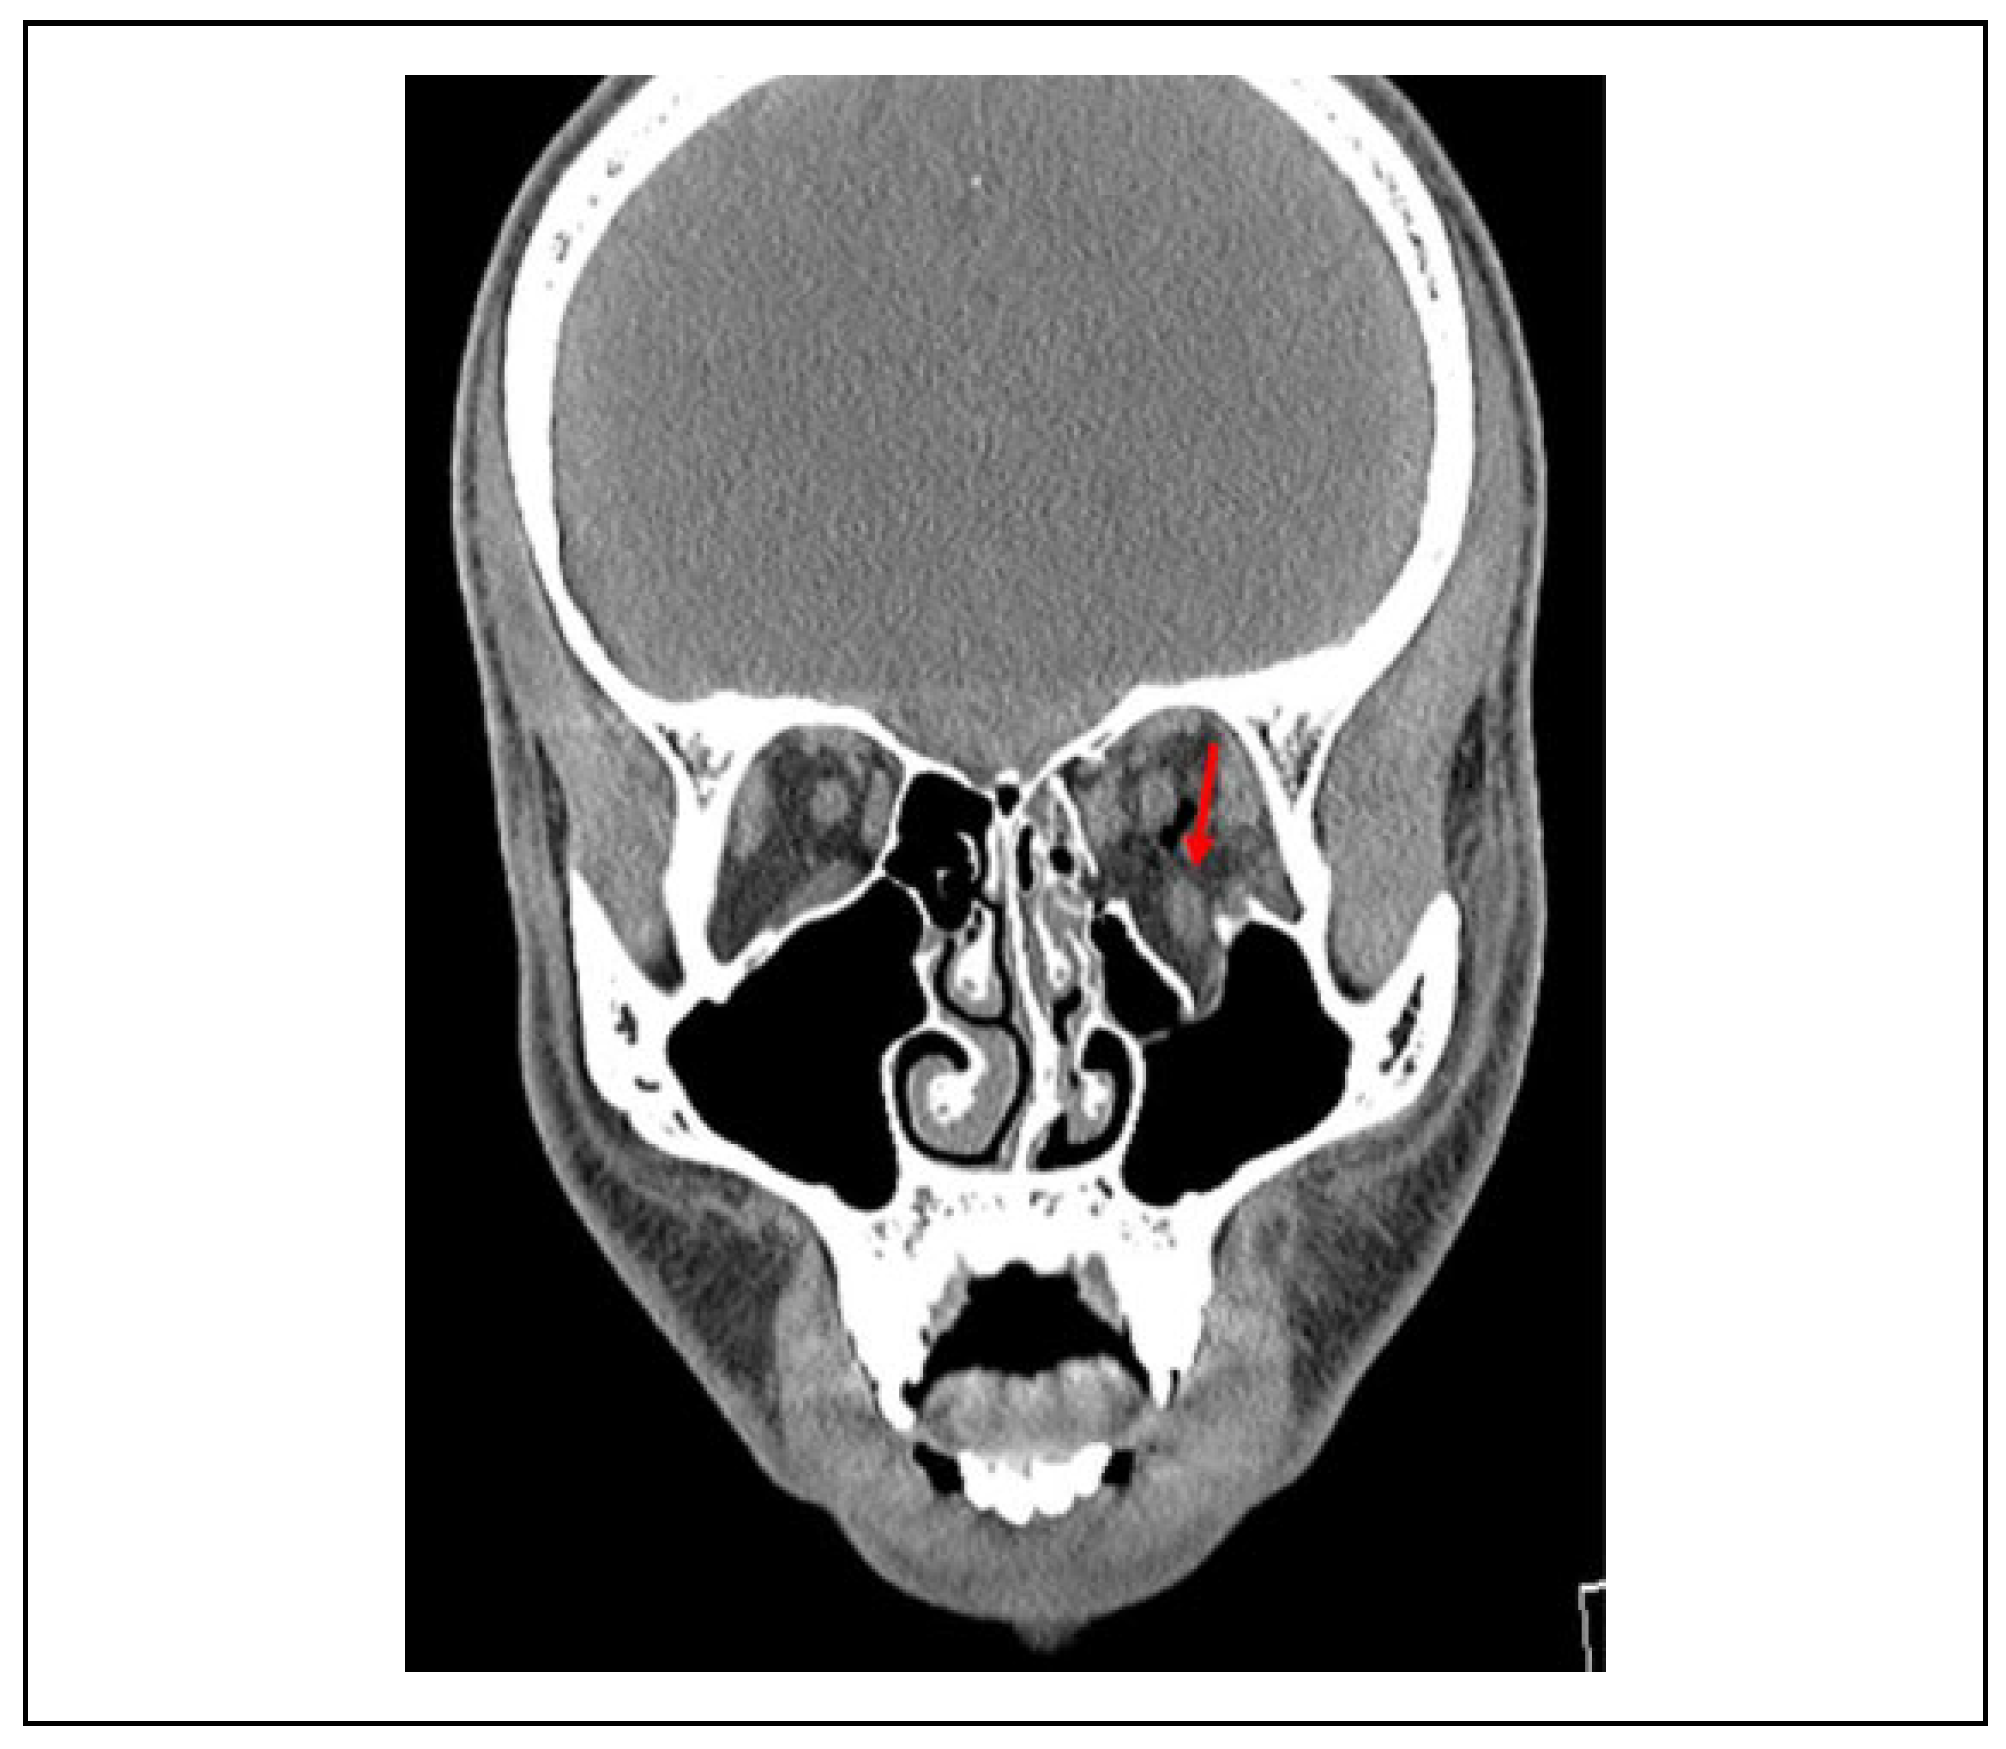

Indications and Timing of Repair

Delayed Repair